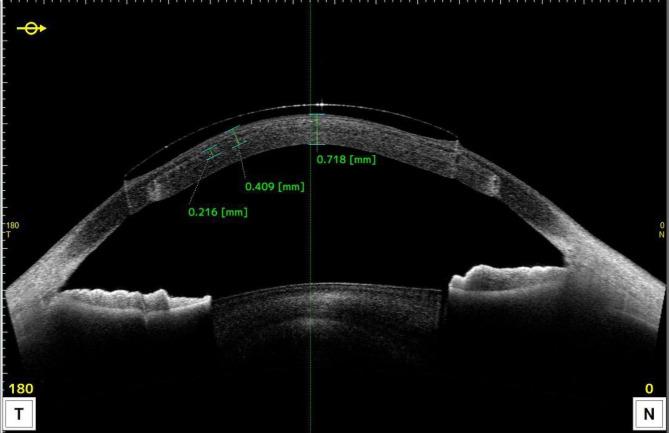

This study aims to observe the clinical efficacy and safety of rigid gas permeable corneal contact lenses (RGP-CLs) wearing after femtosecond laser-assisted minimally invasive lamellar keratoplasty (FL-MILK) in progressive and advanced keratoconus eyes. Twenty-five patients (27 eyes) fitted with RGP-CLs after FL-MILK were enrolled, and 22 grading-matched keratoconus patients (23 eyes) as a control group. Corneal morphological data, diopter, best corrected vision, corneal endothelium, non-invasive tear film rupture time (NIBUT), corneal perception and comfort questionnaire were analysed before and after wearing RGP-CLs. In the FL-MILK group, the flat K, steep K and Kmax of the corneal anterior surface were decreased by 3.05D, 3.48D and 7.17D respectively after surgery (P = 0.011, 0.004 and 0.007). The central corneal thickness increased by 175.29 μm (P < 0.001). The basic curve of RGP-CLs after surgery was about 0.23 mm flatter than that before surgery (P = 0.013). There was no statistical difference in the best corrected vision and the comfort of wearing RGP-CLs before and after FL-MILK (P = 0.923, 0.391). Compared with the control group, there was no significant difference in vision improvement by RGP-CLs (P = 0.669). During the follow-up, the comfort of wearing RGP-CLs in the two groups was good, and no obvious adverse events were observed. This study showed MILK significantly increases corneal thickness and flattens corneal curvature, achieving good RGP-CLs corrected vision.

本研究旨在观察飞秒激光辅助微创板层角膜切削术(FL-MILK)后硬性透气性角膜接触镜(RGP-CL)在进展性和晚期圆锥角膜眼中的临床疗效和安全性。共纳入 25 例(27 只眼)FL-MILK 术后佩戴 RGP-CL 的患者,并选择 22 例分级匹配的圆锥角膜患者(23 只眼)作为对照组。分析佩戴 RGP-CL 前后的角膜形态学数据、屈光度、最佳矫正视力、角膜内皮细胞、非侵入性泪膜破裂时间(NIBUT)、角膜知觉和舒适度问卷。FL-MILK 组术后角膜前表面平 K、陡 K 和 Kmax 分别降低 3.05D、3.48D 和 7.17D(P=0.011、0.004 和 0.007)。中央角膜厚度增加 175.29μm(P<0.001)。术后 RGP-CL 的基本曲线比术前平坦约 0.23mm(P=0.013)。FL-MILK 前后佩戴 RGP-CL 的最佳矫正视力和舒适度无统计学差异(P=0.923、0.391)。与对照组相比,RGP-CL 对视力的改善无显著差异(P=0.669)。在随访过程中,两组佩戴 RGP-CL 的舒适度均良好,未观察到明显的不良事件。本研究表明,MILK 可显著增加角膜厚度并使角膜曲率变平,从而获得良好的 RGP-CL 矫正视力。